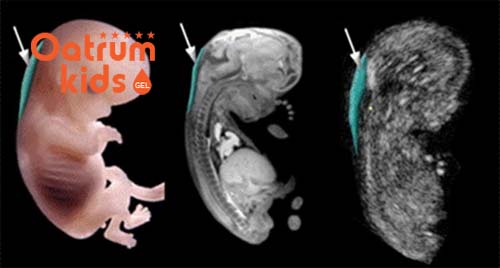

Khi tiến hành đo khoảng sáng sau gáy bác sĩ sẽ đo chiều dài tính từ đỉnh đầu của thai nhi đến cuối xương sống thai nhi, tiếp tục đo độ mờ da gáy. Đây chính là đường trắng ở sau gáy của thai nhi trong khi vùng xung quanh có màu tối sẫm hơn. Đó cũng là lý do vì sao người ta gọi là khoảng sáng sau gáy.

Giai đoạn từ 11 đến 14 tuần tuổi chính là ngưỡng thời gian giúp bác sỹ chẩn đoán rõ nhất chỉ số độ mờ da gáy. Nếu như chẩn đoán sớm, trước 11 tuần thì lúc đó thai nhi còn quá nhỏ nên sẽ chưa rõ và chưa chính xác. Còn nếu như thực hiện đo quá muộn khi thai đã ngoài 14 tuần thì da gáy của trẻ đã dần trở về trạng thái bình thường nên lúc này kết quả sẽ chẳng còn ý nghĩa vì không thể phát hiện ra được.